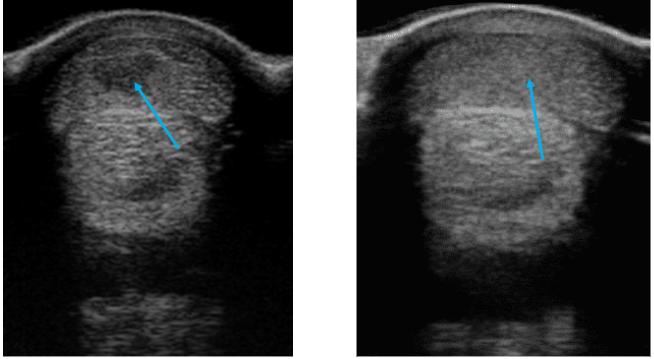

This racehorse presented with Grade 3/5 lameness after the final pre-race gallop and received laser therapy to assist in dispersing the edema within the tendon tear and to accelerate the healing process. The expected rehabilitation time is approximately 18 months. With the use of an Equine Laser Therapy laser, the tendon recovery appeared on ultrasound examination to be 4 weeks ahead of usual.

BEFORE LASER AFTER LASER